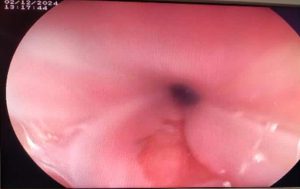

Laboratory tests showed normal complete blood count (CBC), serum creatinine, and liver enzymes. The stool Helicobacter pylori (H. pylori) antigen test was negative. Upper GI endoscopy revealed salmon-colored mucosa approximately 17 cm from the incisors in the proximal esophagus (Figure 1). She started on pantoprazole 40 mg per oral (PO) daily and was scheduled for the next visit after 1 month. There was a significant improvement in symptoms during her follow-up visit.

Figure 1: Salmon-colored mucosa at the proximal esophagus (17cm from the incisors)